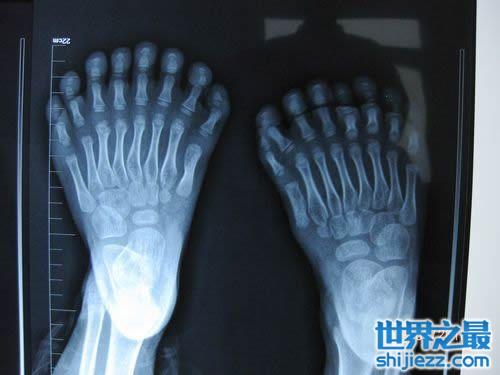

一个叫鹏鹏的小朋友,他的手指和脚趾长得“很特别”,小鹏鹏的手指有15根,脚趾有16根,加起来就是31根,令人奇怪的是,他的每只脚上都长有8根脚趾,且长得还很匀称,散开看酷似“莲花掌”,而手指长得就更奇了,有散开长的,还有并着长在一起的,一只手长有7根,另一只是8根,成为世界上手指和脚趾最多的人。

小鹏鹏的脚趾有16根